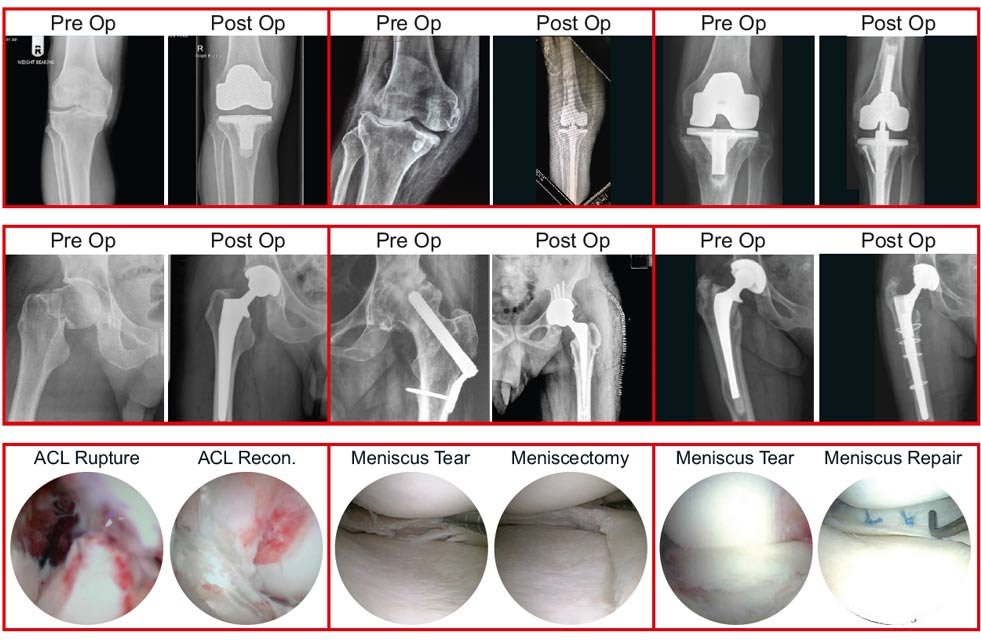

Joint Replacement Surgeries

HIP

KNEE

ANKLE

Sports Injury Surgeries

KNEE ARTHROSCOPY